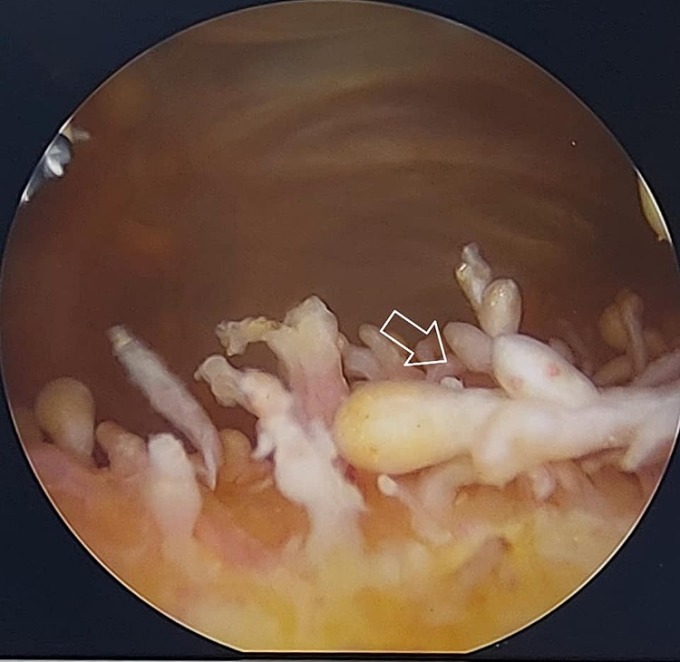

Bệnh nhân 63 tuổi viêm màng hoạt dịch khớp gối quá lâu khiến màng hoạt dịch tua rua hiếm gặp, bác sĩ nội soi nhìn thấy hình ảnh như "cánh đồng nấm".

Bác sĩ Hiền chỉ định nội soi khớp gối bệnh nhân, kết quả hình ảnh là niêm mạc hoạt dịch trong khớp gối tua rua, chỗ đỏ rực, chỗ lại trắng, cái to cái nhỏ, như cánh đồng nấm. Khi nhìn thấy hình ảnh nội soi viêm khớp gối của bệnh nhân, anh rất bất ngờ liền chia sẻ lại với đồng nghiệp.

Bác sĩ cho biết bình thường màng hoạt dịch tại khớp gối nhẵn bóng. Khi viêm khớp lâu ngày, màng hoạt dịch rất dày, các nhung mao màng hoạt dịch gần như mắt thường nhìn sẽ phẳng lỳ, kể cả khi nội soi, phóng đại đến 4 lần "cũng không bao giờ thấy hình ảnh nào đặc biệt như thế".

Một vài đồng nghiệp của bác sĩ Hiền sau đó đăng tải ảnh "viêm khớp như cánh đồng nấm" lên mạng xã hội nhận được nhiều lượt like và chia sẻ. Nhiều người còn ví hình ảnh như đông trùng hạ thảo trong khớp gối bệnh nhân.

Hình ảnh niêm mạc màng hoạt dịch trong khớp gối bệnh nhân giống như một cánh rừng nấm. Ảnh: Bác sĩ cung cấp

Bác sĩ Hiền cho biết, khớp của bệnh nhân này tràn dịch nhiều, đầu gối biến dạng sưng to, màng dịch dày, kết quả chụp, chiếu, xét nghiệm thấy tăng axit uric trong máu, thoái hóa khớp độ 3, viêm dày màng dịch, các sụn của khớp có chỗ bị bong tróc. Bác sĩ chẩn đoán viêm màng hoạt dịch khớp gối. Đây là tình trạng viêm túi chứa dịch lỏng ở khớp gối. Màng hoạt dịch giúp giảm ma sát và là miếng đệm chịu lực giữa hai đầu xương và gân, cơ, da gần khớp.

Ê kíp mở nội soi chọc hút ra nhiều dịch màu nâu đen, sau đó rửa khớp sạch sẽ, nhìn thấy màng dịch dày, tua rua như cánh đồng nấm liền cắt sạch màng dịch, tái tạo sụn. Sau phẫu thuật, bệnh nhân sức khỏe ổn định, ngủ ngon.